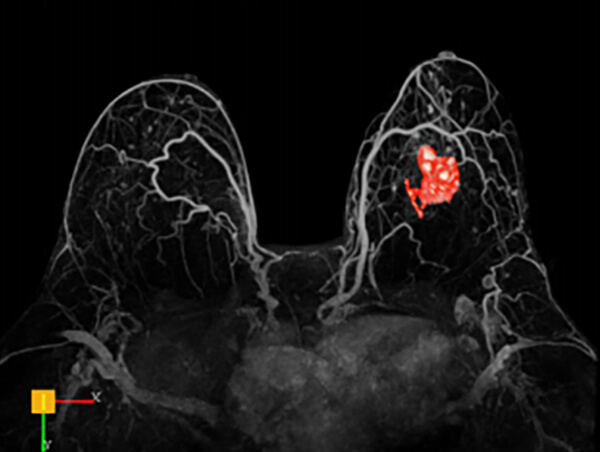

Τρισδιάστατη απεικόνιση ταχείας πρώιμης αιμάτωσης μαστών

- Εφαρμόζεται στο τμήμα μας από εξειδικευμένους ιατρούς*, με τη χρήση ειδικών τεχνικών πολυπαραμετρικής μελέτης και μετεπεξεργασία δεδομένων σε σύστημα CAD (computer aided diagnosis)

- Δυναμική αγγειογραφία (4D time resolved TWIST)

- Επεξεργασία των δεδομένων σε σύστημα CAD